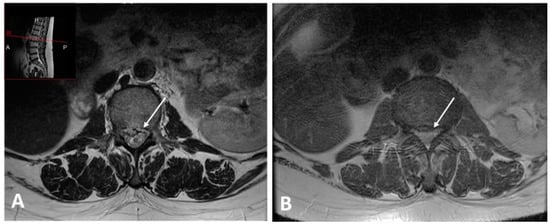

Accordingly, the patient was diagnosed with severe lumbar intervertebral disc degeneration with diffuse bulge, as identified by magnetic resonance imaging (MRI) in March 2017, using a multiple sagittal and axial T1 and T2 sequences. The examination was performed on a 3 Tesla, which revealed a large central L2–L3 disc herniation with upward migration compromising the spinal canal, dural sac, and neural elements that explained the painful symptomatology (Figure 1A), with urgent indications for surgical intervention. No other diseases (i.e., coronary heart disease, stroke, metabolic diseases) were reported.

The patient completed the CBT-OB programme on 12 September 2018. At this time, her body weight had fallen to 73.5 kg and her BMI to 27.8 kg/m2—a weight loss of 16%, and there was a clear improvement in pain symptoms from intervertebral disc degeneration. This was corroborated by MRI imaging repeated in March 2018, which revealed a significant regression of the large L2–L3 disc extrusion (Figure 1B). On that basis, the consultant surgeon gave no further indications for intervention. The InBody body composition assessment was repeated and revealed improvements, with a significant decrease in total and central body fat (FM% = 38.1%, trunk fat percentage = 39.6%, visceral fat level = 9) and no deterioration in skeletal mass (SMM = 24.5 kg) (Table 1). The blood test revealed a significant increase in high-density lipoprotein (HDL) cholesterol (65 mg/dL; normal values of >55 mg/dL), which is known to be associated with a lower risk of heart disease [10] (Table 1).

Figure 1. MRI image before weight loss shows a large central L2–L3 disc herniation compromising the spinal canal (A). After weight loss a significant regression of the large L2–L3 disc extrusion (B).